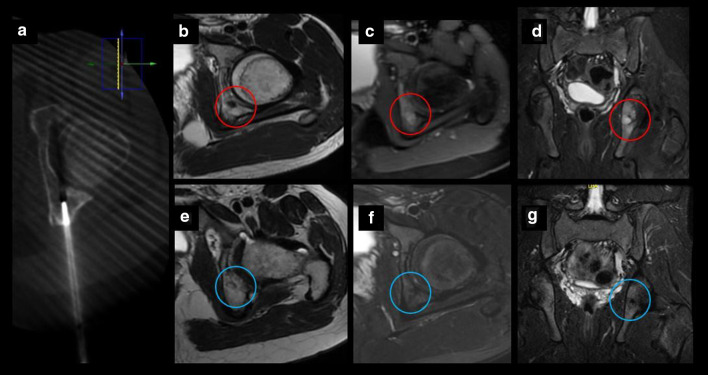

Chondroblastoma in a 14-y.o patient. a Axial CT exhibiting one cryoprobe placed within the lesion. b–d MRI images demonstrating a small tumor in the left posterior acetabulum corresponding to chondroblastoma (red circle). e–g Follow-up MRI images 20 months after treatment with no evidence of recurrence (blue circle)

The medical literature cites an overall complication rate of 9.1% associated with cryoablation of bone lesions and a major complication rate of 2.5%. Secondary fracture is the most common major complication of bone tumor cryoablation, occurring in approximately 1% of patients [16]. Some of the immediate complications of cryoablation are related to thermal damage to nearby structures. Different techniques to protect the critical structures at risk of being injured have been described in the medical literature; furthermore, the insulating techniques improve the safety of the procedure for complex lesions in challenging locations [17]. In this series, air and hydrodissection were used in 5 patients to protect adjacent cartilage from the ablation zone used to treat intra- or juxta-articular lesions. In this series, one immediate moderate complication (according to the Society of Interventional Radiology (SIR) [9] has been observed: periprocedural, right L2–L3 transient radiculopathy after the treatment of an osteoblastoma located in the body of the 11th thoracic vertebra. Despite the injection of diluted contrast in the epidural space and the neurophysiological and thermal control during the procedure (that showed no alterations), the patient experienced pain and difficulty lifting the right foot after the intervention without sensory deficit. Due to restrictions on in person clinic visits secondary to SARS CoV2 pandemic, telephone consultation 4 months after treatment was made. During the telemedicine appointment, complete resolution of symptoms was confirmed. Neurological consultation 12 months after the intervention confirmed the resolution of radiculopathy symptoms with normal physical examination, normal sensation and motor control, as well as complete resolution of the lesion on the follow-up thoracic spine MRI.